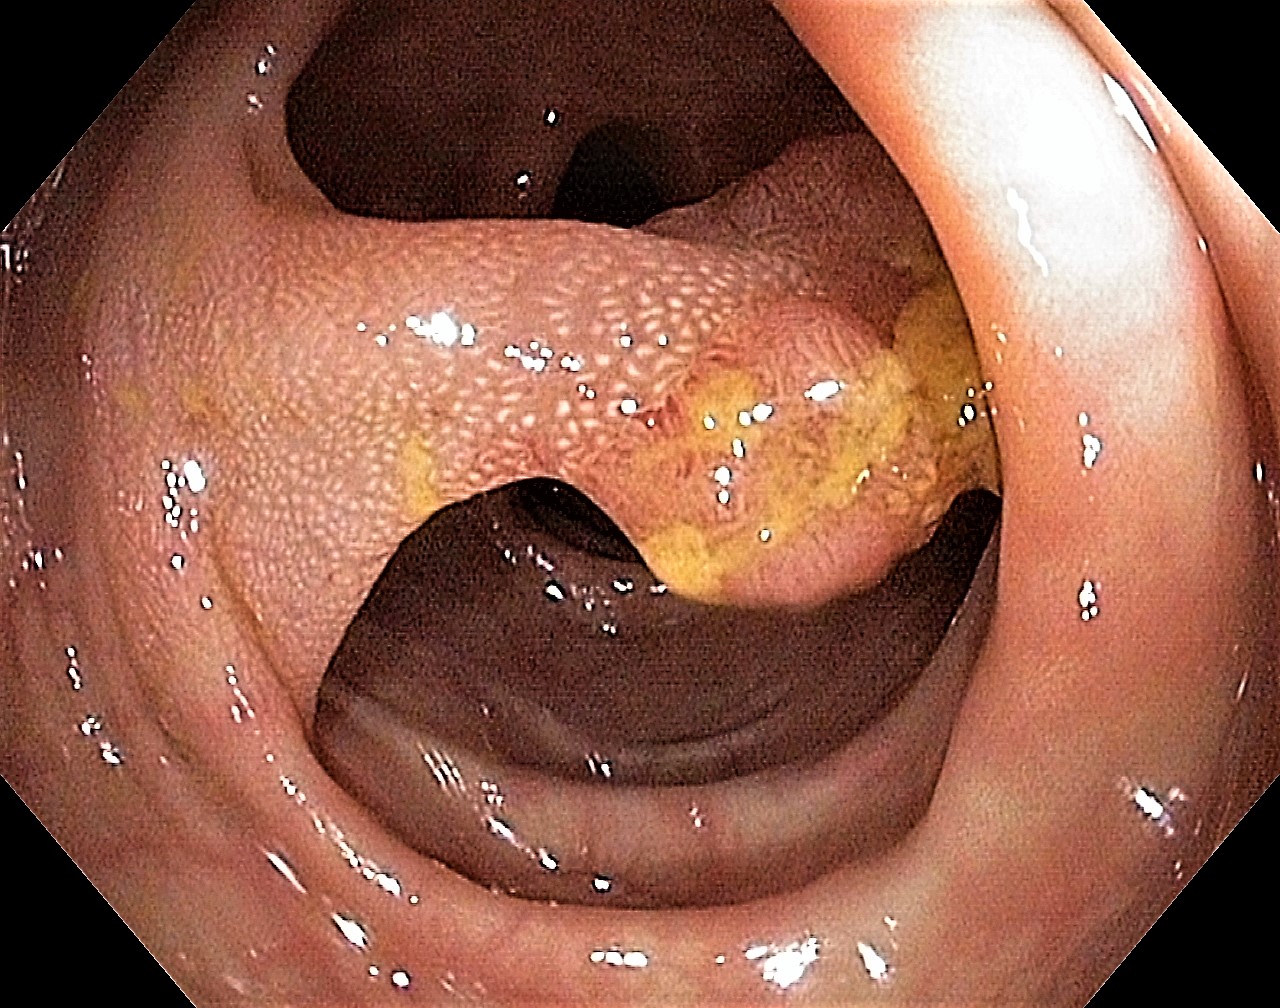

Sigmoid Tubular Adenoma with Chicken Skin Mucosa

Slight Mucosal Changes are frequently seen adjacent to a colorectal cancer or adenomas. First described by Shatz BA et al, they are called Chicken Skin Mucosa (CMS), and are supposed to occur as a result of fat accumulation in macrophages in the lamina propria adjacent to colonic neoplasms. In a series of 852 consecutive colonoscopies CMS was found adjacent to eight of 10 distal colorectal cancers, one of four of proximal colon cancers and 16 of 42 distal adenomas.

Shatz BA, Weinstock LB, Thyssen EP, Mujeeb I, DeSchryver K: Colonic chicken skin mucosa: an endoscopic and histological abnormality adjacent to colonic neoplasms. Am J Gastroenterol 1998 Apr;93(4):623-7